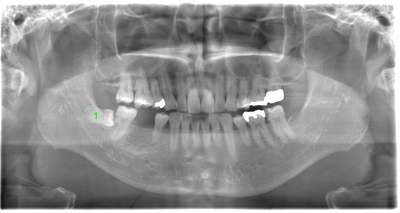

CASE 1

| 年齢・性別 | 30代・女性 |

| 主訴 | 左右に分けて親知らずを抜きたい、できれば痛くなく抜きたい |

| 親知らずのはえ方 | 完全に出ていてまっすぐはえている |

| 抜歯期間 | 15分 |

| 抜歯費用 | 約2,000円(保険内) |

| 抜歯内容 |

何度か虫歯になり痛みはないが早めに抜きたい。 完全に頭が出ているため歯ぐきを切ったり骨を削らずに抜歯しました。 根の形も単純なため抜歯自体は5分もかからず上下ともに終わりました。 術後痛みや腫れも出ていません。 抜歯後は感染をしやすいため必ず抗生物質を飲み切ってください。 |